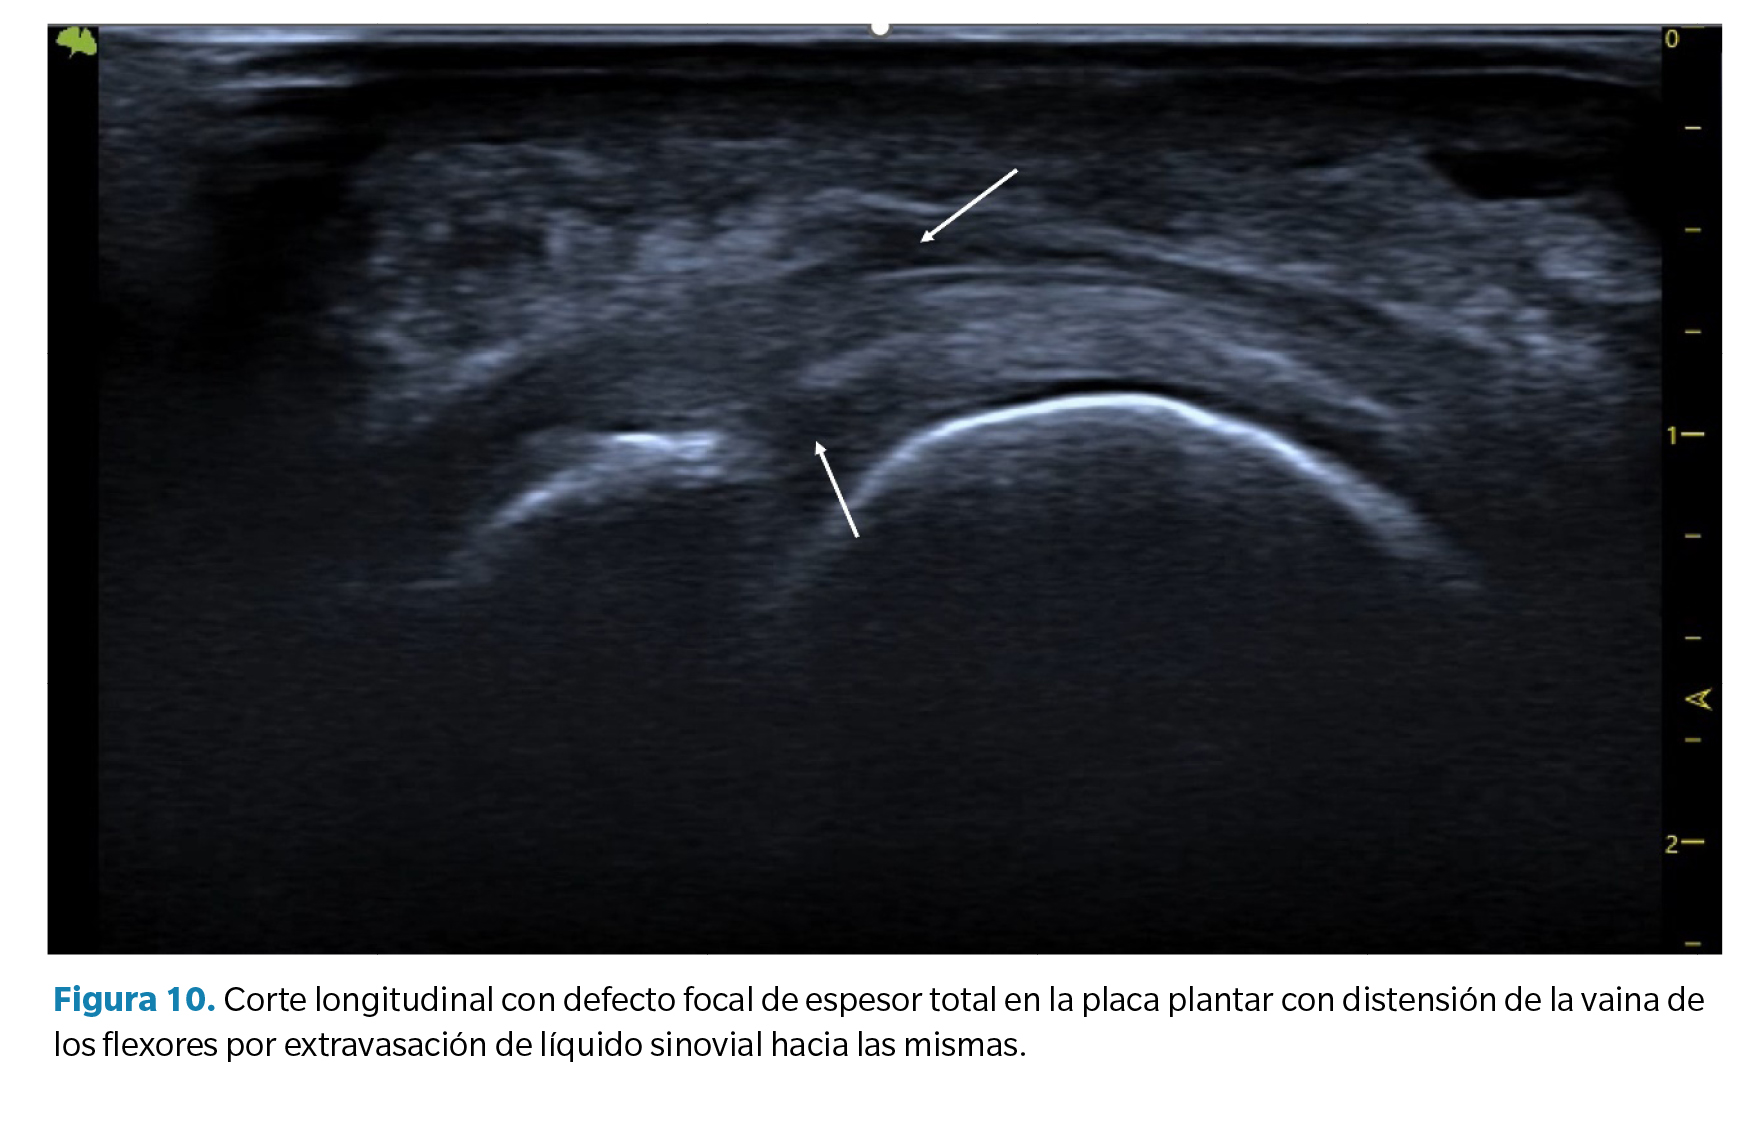

- Líquido articular (sinovitis) plantar o dorsal. Derrame sinovial. Como la placa plantar constituye el cierre plantar de la cápsula articular, los desgarros de la placa pueden dar lugar a un aumento significativo del líquido sinovial que se manifiesta como un derrame sinovial apreciable a nivel dorsal y a nivel plantar. En algunos casos este líquido puede filtrarse hacia los tendones flexores manifestando un halo hipoecoico en los mismos que se asemeja a la imagen característica de una tenosinovitis con distensión de la vaina tendinosa (Figura 10).